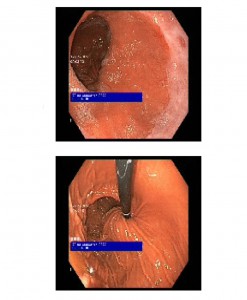

Endoscopia oral: Desplazamiento de la banda gástrica sin penetración de la misma a estómago. Esofagitis grado A.